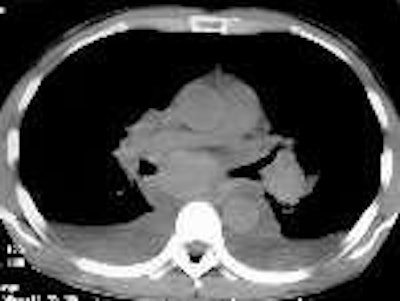

The patient was then referred for a chest CT exam. The procedure was conducted on a LightSpeed (GE Medical Systems, Waukesha, WI) spiral scanner. No contrast was used, and a standard 7-mm slice thickness chest protocol was employed.

Cerva observed a profuse and slightly hyper-attenuating paratracheal, anteroposterior (AP) window, subcarinal, hilar, and azygo-esophageal recess lymphadenopathy. In addition there was diffuse mediastinal edema, bilateral pleural effusions, bibasilar airspace disease, more pronounced on the left, and thickened peribronchial tissue (seen best on lung windows).

A noncontrast CT scan was performed on the patient using the institution’s standard chest protocol. Berman found a profuse and slightly hyper-attenuating paratracheal, AP window, subcarinal, hilar, and azygo-esophageal recess lymphadenopathy similar to what Cerva had observed a few hours earlier in the first patient.

She also saw diffuse mediastinal edema, bilateral pleural effusions, and thickened peribronchial tissue. In this patient, however, bibasilar airspace disease was more pronounced on the right.